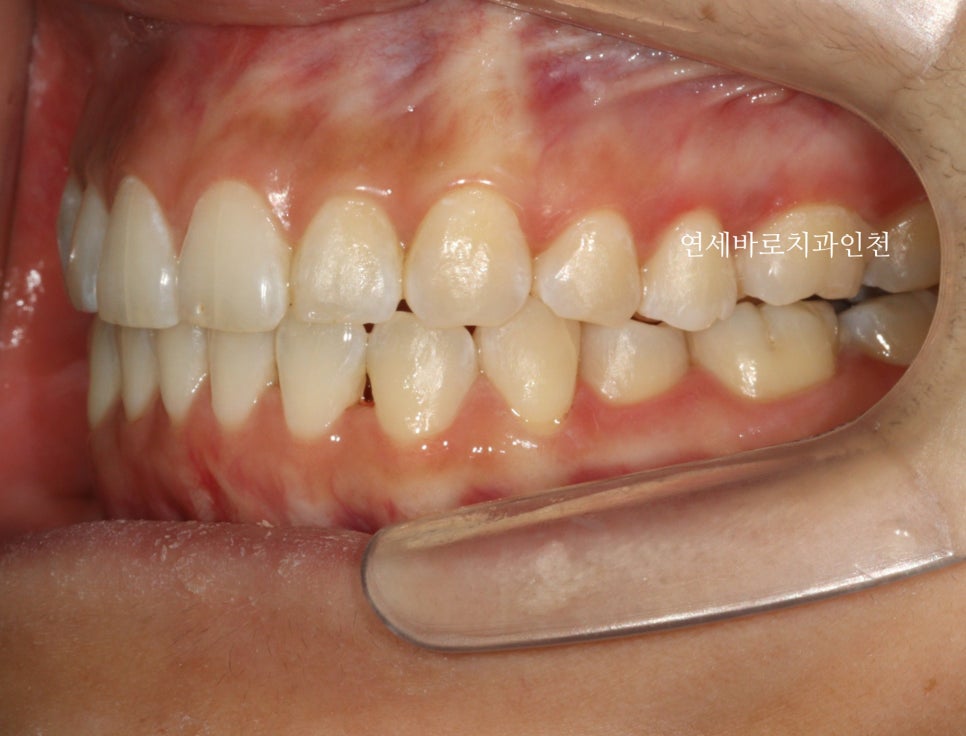

교정이 마무리되고 보면 문제없죠?

전후 측면 모습입니다.

치아가 확실히 후방이동을 하며 배열되었습니다.

조금 더 자연스러운 입술의 위치를 확인할 수 있었습니다.